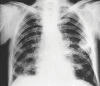

Musculoskeletal tuberculosis (TB) accounts for approximately 10% of all extrapulmonary TB cases in the United States and is the third most common site of extrapulmonary TB after pleural and lymphatic disease. Vertebral involvement (tuberculous spondylitis, or Pott's disease) is the most common type of skeletal TB, accounting for about half of all cases of musculoskeletal TB. The presentation of musculoskeletal TB may be insidious over a long period and the diagnosis may be elusive and delayed, as TB may not be the initial consideration in the differential diagnosis. Concomitant pulmonary involvement may not be present, thus confusing the diagnosis even further. Early diagnosis of bone and joint disease is important to minimize the risk of deformity and enhance outcome. The introduction of newer imaging modalities, including MRI (imaging procedure of choice) and CT, has enhanced the diagnostic evaluation of patients with musculoskeletal TB and for directed biopsies of affected areas of the musculoskeletal system. Obtaining appropriate specimens for culture and other diagnostic tests is essential to establish a definitive diagnosis and recover M. tuberculosis for susceptibility testing. A total of 6 to 9 months of a rifampin-based regimen, like treatment of pulmonary TB, is recommended for the treatment of drug susceptible musculoskeletal disease. Randomized trials of tuberculous spondylitis have demonstrated that such regimens are efficacious. These data and those from the treatment of pulmonary TB have been extrapolated to form the basis of treatment regimen recommendations for other forms of musculoskeletal TB.